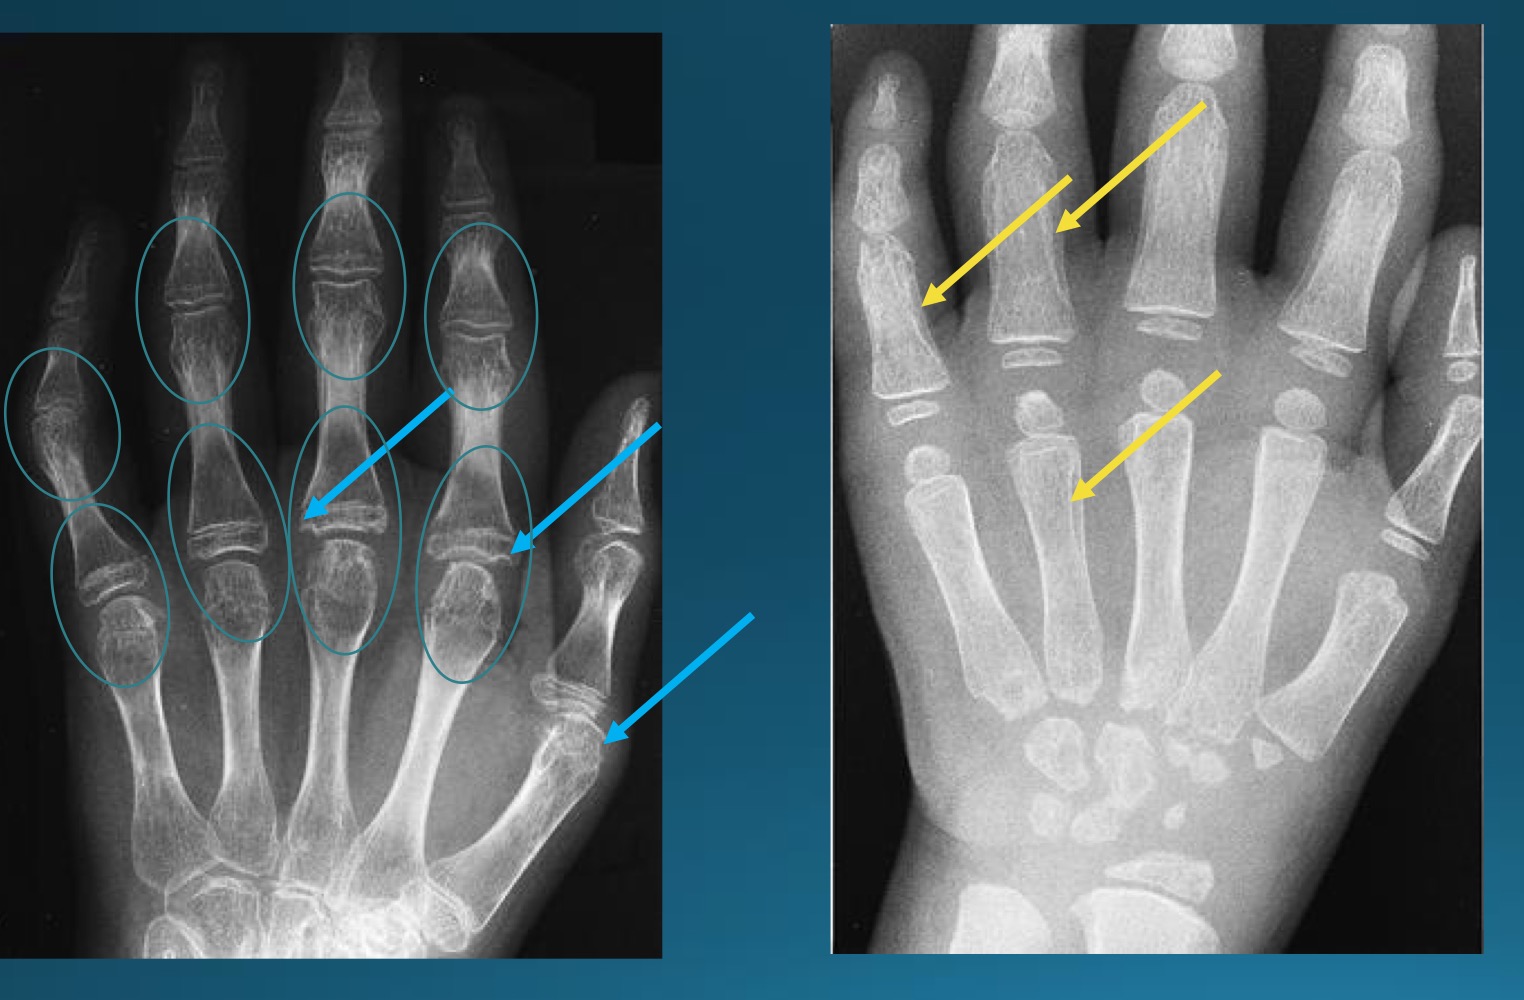

what are the findings in this image?

erosive osteoarthritis

waht are the features denoting erosive osteoarthritis on radiograph?

central erosions creating gull wing sign

EOA likes what joints?

DIP, PIP, 1st CMC